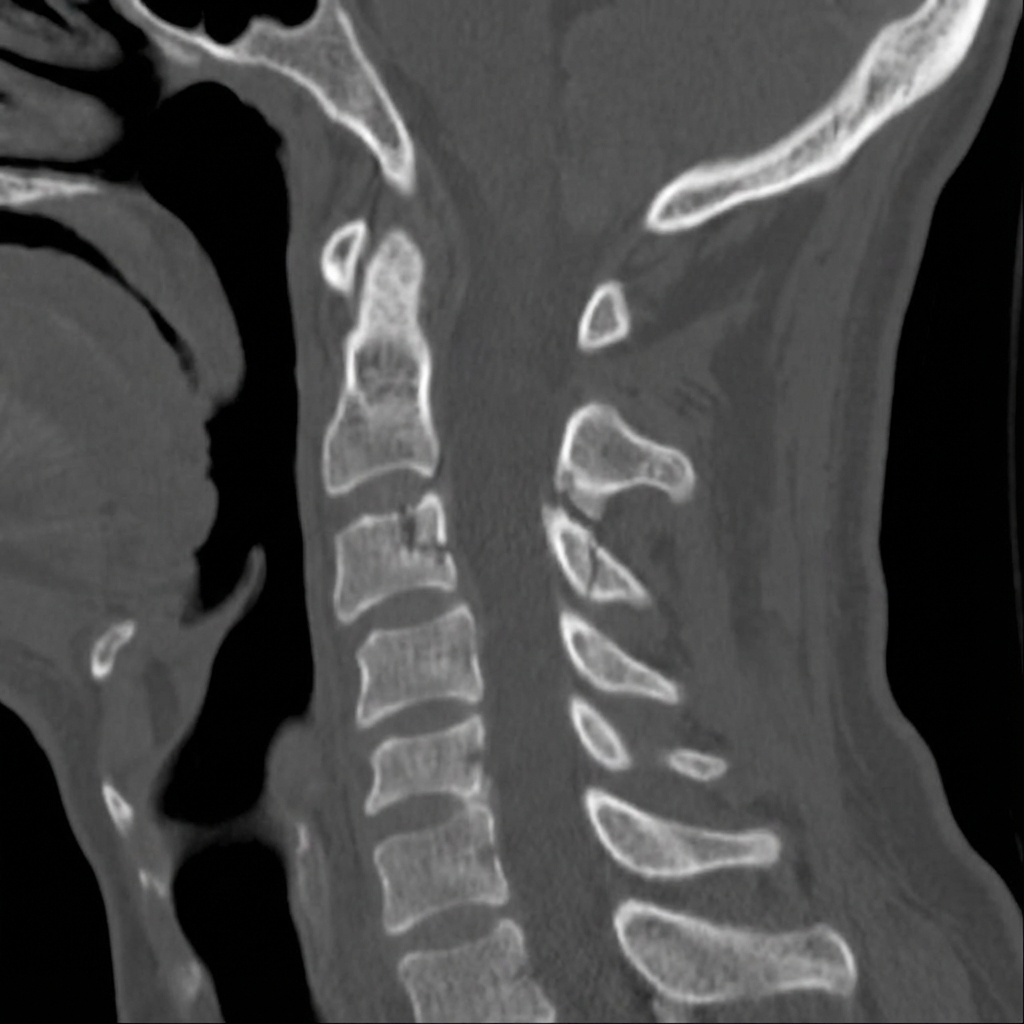

Sagittal and axial CT images demonstrating bilateral fractures through the pars interarticularis of C2 (hangman's fracture). There is anterior displacement of C2 on C3 with disruption of the C2-3 disc space. The fracture lines extend through the pars bilaterally. This represents a Type II hangman's fracture requiring consideration of surgical stabilization.

Describe the CT findings and classify this fracture.